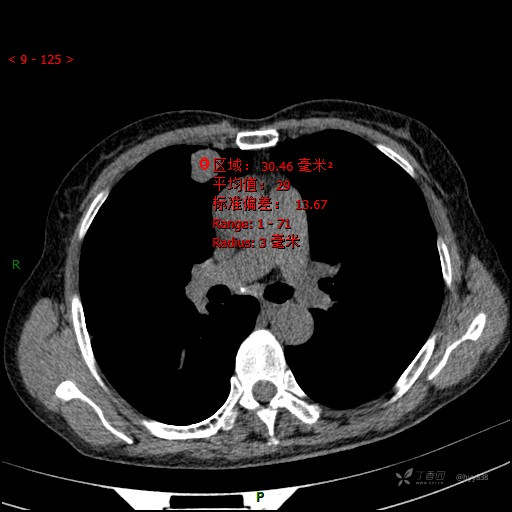

CT值